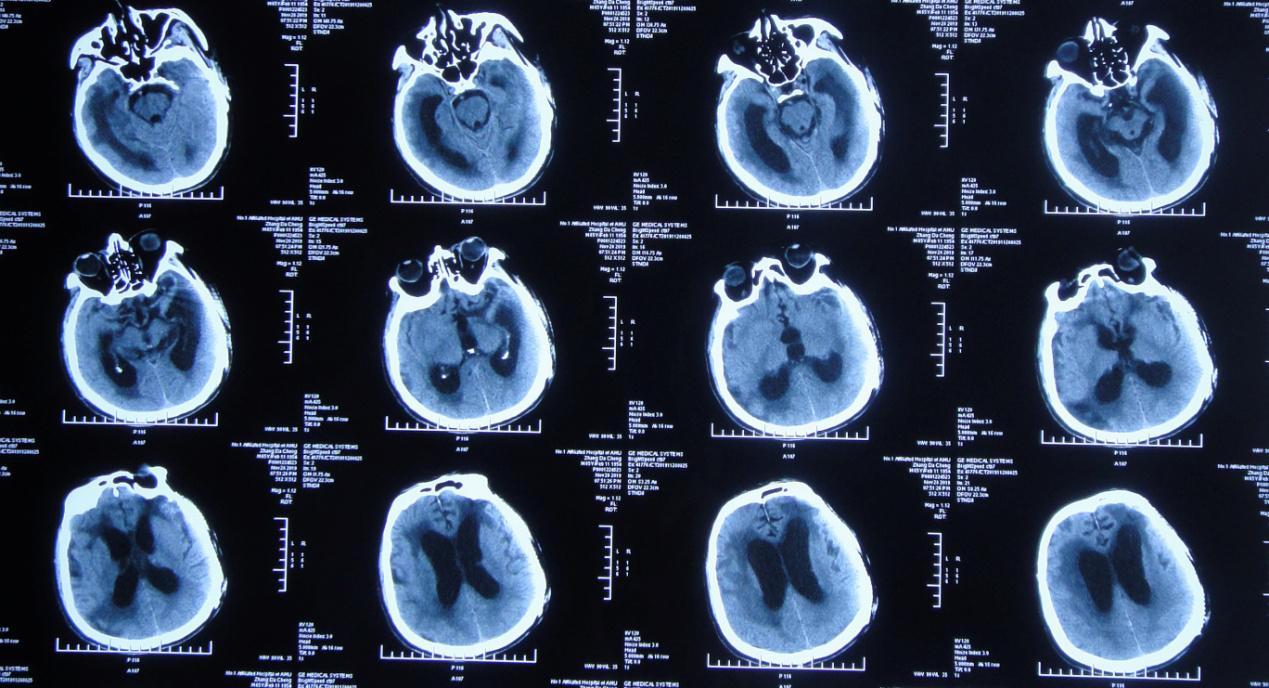

患者2019年7月10日骑电动自行车不慎与大货车相撞,当时意识模糊,可简单对答,四肢可见活动。由120急送至当地安徽省六安市某医院,行头颅CT示大脑多发挫伤(片子丢失),给予甘露醇等脱水治疗,效果差,意识明显加重,呼之不应,呈昏迷状态。当日急转入上级的安徽省某知名省级三甲医院,行头颅CT( 图-1 )示左颞叶脑挫伤伴血肿形成,右额叶脑挫伤,蛛网膜下腔出血,脑疝。

图-1: 2019年7月10日术前头颅CT